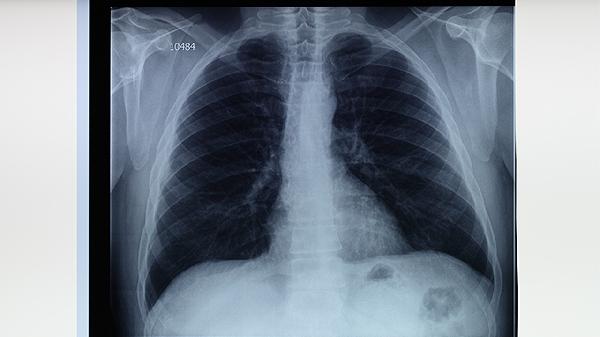

肺结核患者未完成全程规范用药是导致复发的主要原因。部分患者在症状缓解后自行停药,使体内结核分枝杆菌未被彻底清除。世界卫生组织推荐的标准化治疗方案需要持续用药6个月以上,过早中断治疗易诱发细菌耐药性。患者应严格遵循医嘱用药,定期复查胸部影像学变化。